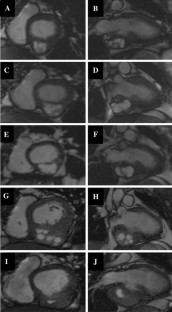

Fig. 2